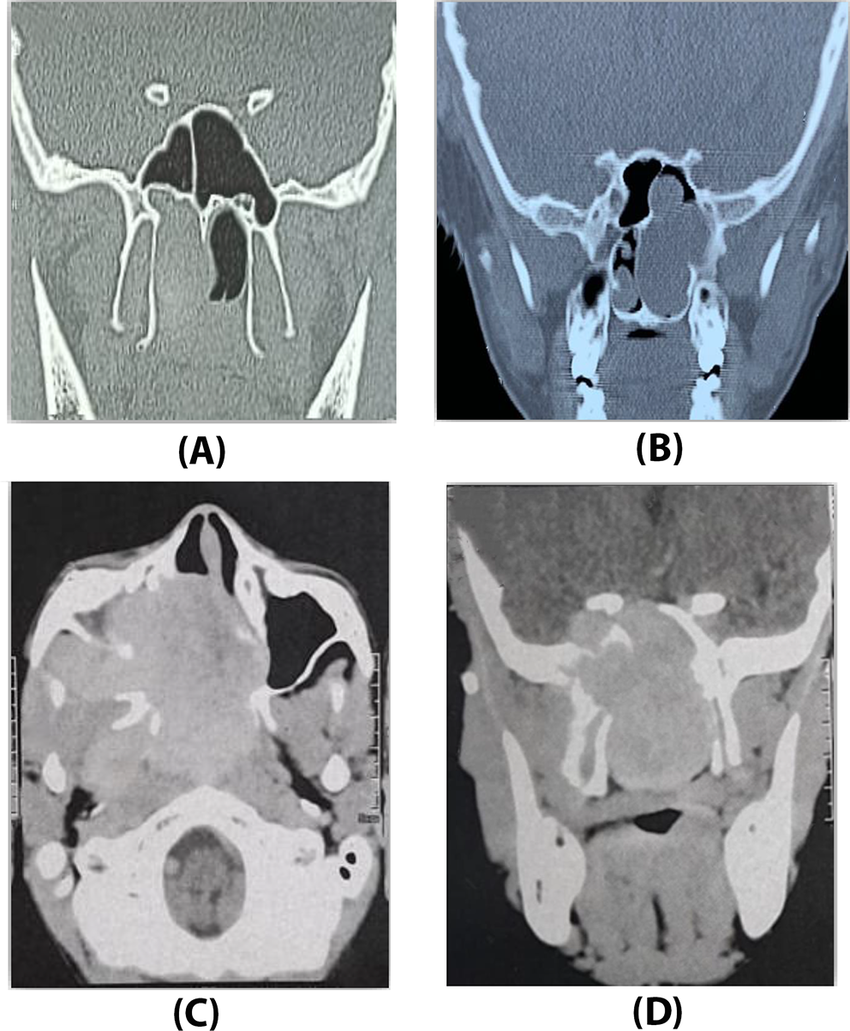

Choanal atresia surgery: outcomes in 42 patients over 20 years and a review of the literature

يتناول هذا البحث جراحة انسداد القناة الخلفية للأنف (Choanal Atresia) ونتائجها على مدار 20 عامًا، بناءً على دراسة 42 مريضًا. أظهرت النتائج أن الحالات الثنائية والأمراض المصاحبة تزيد من عدد العمليات الجراحية المطلوبة. وخلص البحث إلى أن هناك زيادة في معدل تضيق الشريان التاجي لدى مرضى رتق القناة الأنفية الثنائي وارتجاع المريء والأمراض المصاحبة، مع التأكيد على ضرورة إبلاغ أولياء الأمور باحتمالية الحاجة لجراحة مراجعة.